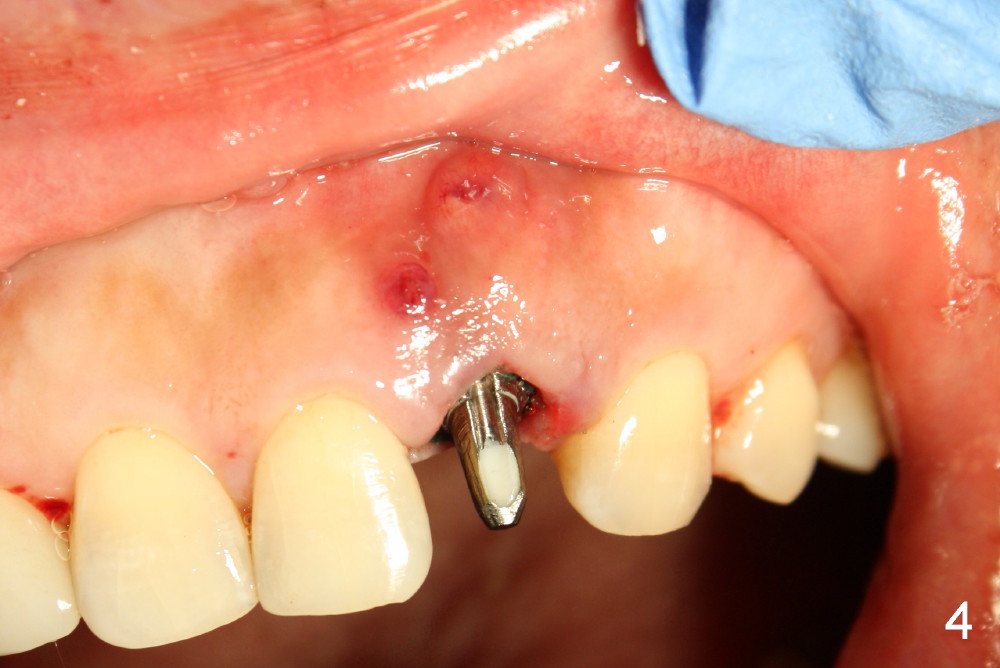

A 49-year-old lady has failed endo on the upper left lateral incisor (Fig.1,2). A gutta percha inserted to the buccal fistula (Fig.1 >) shows a mesial defect (Fig.2<). There is a large buccal apical defect, corresponding to the lesion shown in Fig.2 *, when the affected tooth is extracted. After thorough debridement and Clindamycin soaking, osteotomy is initiated in the palatal wall of the socket. Demineralized freeze dry cancellous bone graft is placed in the buccal defect. A 4x20 mm gingiva-level tapered implant is placed with insertion torque 50 Ncm (Fig.3). A 3x5 mm 20 ° offset abutment is inserted and cemented (Fig.4,5). A retentive groove is prepared on the abutment and the underlying implant; chamfer margin placed on the implant (Fig.4,5). A provisional is fabricated and cemented temporarily (Fig.6,7). Excess cement is removed, followed by removal of gingival retraction cord. There is no contact in centric and non-centric occlusion.